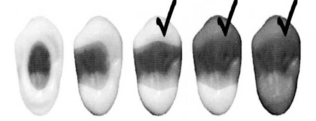

3. Дизайн двойной конусности

В 1990 эндодонтологи и ортопеды университета г. Монреаль решили создать такой дизайн штифта, который мог быть припасован к корневому каналу, вместо того, чтобы припасовывать канал к форме штифта. Как результат этой идеи появился DT штифт двойной конусности. Для того, чтобы определить анатомическую форму, были исследованы 967 каналов удаленных зубов ранее подвергнутых эндодонтическому лечению посредством разных техник. Были проведены сотни измерений и расчетов для того, чтобы разработать форму, оптимальную по диаметру и конусности для всех видов каналов в зубах всех видов. Рентгенологическое исследование в большинстве случаев показывало форму, имеющую двойную конусность, т.е. имеющую меньший диаметр апикальной трети и больший - в коронковой части.

Тонкий штифт изгибается сильнее под меньшей нагрузкой, чем штифт с большим диаметром и с тем же модулем эластичности. Диаметр DT штифта, будучи сравнительно небольшим внутри имеет гибкость, схожую с таковой дентина. Эта стабильность очень важна, так как там, где штифт находится в корневом канале диаметр меньше, а в области коронки или культи диаметр штифта увеличивается (6).Авторы Scotti & Baldassara (8) в результате своих исследований предложили, что в клинических случаях, где коронка полностью раз рушена, штифты с большим диаметром способствуют лучшему сопротивлению смещения центра, следовательно уменьшении риска перелома реставрации.